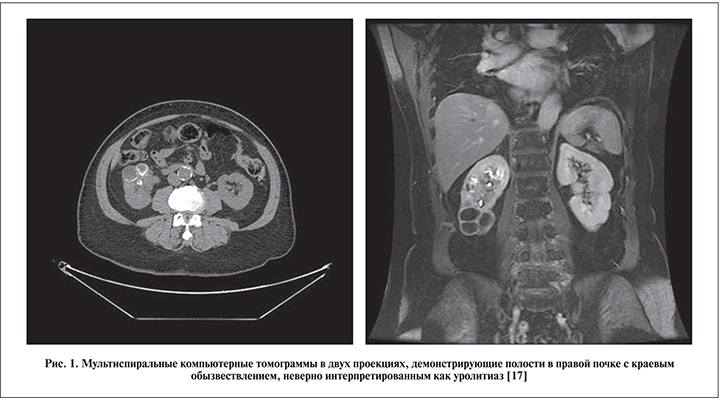

Обсуждение. Проблема дифференциальной диагностики мочекаменной болезни и нефротуберкулеза актуальна во всем мире. В двух статьях описаны наблюдения «сочетания» мочекаменной болезни и нефротуберкулеза у трех жительниц Канады. Мы намеренно взяли слово «сочетания» в кавычки, поскольку пристальный анализ показал, что в этих ситуациях имели место ошибки дифференциальной диагностики. Чернокожей жительнице Канады 76 лет была проведена перкутанная нефролитотомия (так у авторов) по поводу камня нижнего полюса правой почки. Туберкулез у нее все же подозревали, поэтому выполнили посев мочи на микобактерию туберкулеза, но получили отрицательный результат [17]. На рис. 1 хорошо визуализируются полости с краевым обызвествлением. Однако камня, который бы стал показанием к нефролитотрипсии, на наш взгляд, не видно. Тем не менее операцию выполнили, но стенки лоханки оказались настолько воспалены, что было принято решение о проведении биопсии; гистологически обнаружен туберкулез.